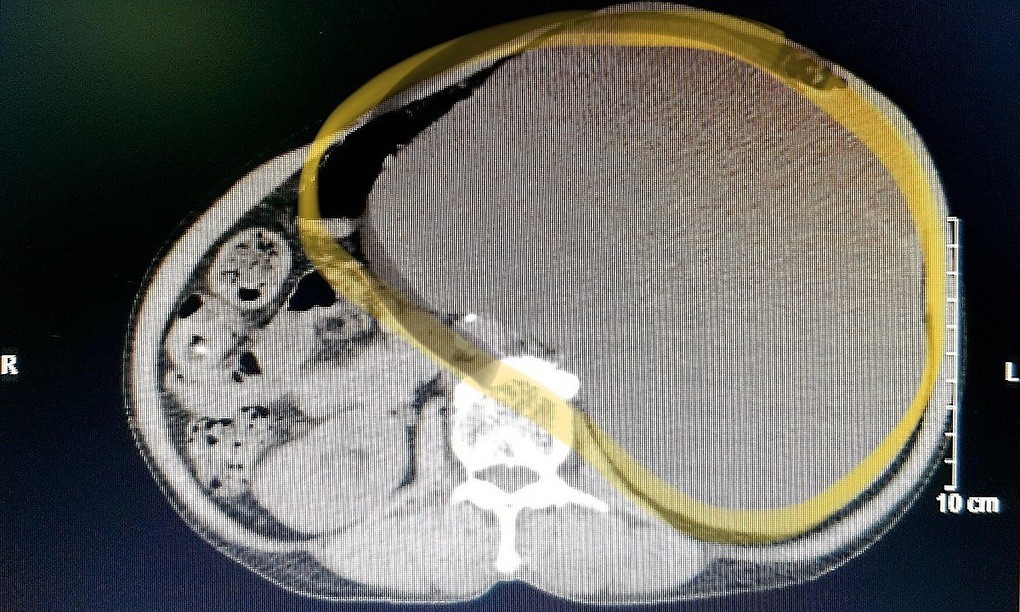

Bệnh nhân 88 tuổi, ở Hưng Yên, nhiều bệnh lý nền, nhiễm nCoV khi điều trị tại Bệnh viện Bạch Mai, đang diễn tiến nặng, phải thở máy.